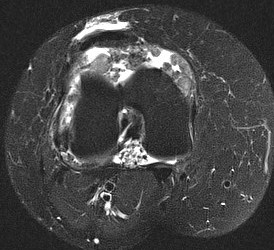

MRI

Synovial Proliferation

Soft tissue lesions same signal intensity as cartilage

Synovial chondromatosis